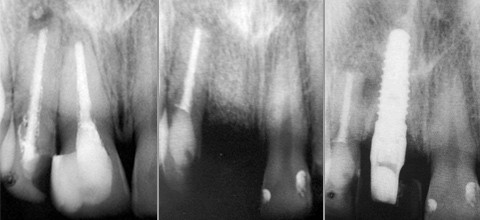

Anhand eines Fallbeispieles soll die Problematik eines mehrfach resizierten Oberkiefer-Frontzahnes erläutert werden, der langzeittherapeutisch nicht zu erhalten war und durch ein Einzelzahnimplantat ersetzt wurde.

Die zum damaligen Zeitpunkt 20-jährige Patientin klagte über immer wieder auftretende Schmerzen im Bereich des Zahnes 11 und 12. Gleichzeitig störte sie die Verfärbung der Zähne, die sich nach endodontischer Versorgung und Resektion des Zahnes 12 alio loco eingestellt hatte. Im Juni 2000 erfolgte nach Absprache in unserer Praxis eine erneute WSR der Zähne 11 und 12. An beiden Wurzelspitzen hatten sich erneut apikale Osteolysen gebildet. Zahn 12 wies intraoperativ einen auch radiologisch erkennbaren Fremdkörper auf, der sich als Wurzelfüllmaterial darstellte (Titelbild links). Um eine weitere Narbe zu umgehen, wurde die alte Schnittführung (Partsch) übernommen und mikrochirurgisch vernäht (Supramid 7/0). Der postoperative Wundverlauf erfolgte komplikationslos und die Patientin war nach ca. einer Woche beschwerdefrei. Dieser Zustand hielt nur etwas mehr als zwei Jahre an, denn dann klagte die Patientin abermals über einen Perkussionsschmerz. Eine weitere Resektion schien therapeutisch als nicht sinnvoll, sodass der Zahn 11 im November 2002 entfernt wurde. Nach Entfernung des Zahnes wurde eine auf Grund von osteolytischen Prozessen entstandene Diskontinuität der bukkalen Knochenlammelle deutlich. Nach Reflektion eines Full-Flap wurde der Defekt mit bovinen Knochenpartikeln (Bio-Oss®, Fa. Geistlich) und einer Kollagenmembran (Bio-Gide®, Fa. Geistlich) augmentiert und abgedeckt. Als provisorischen Verschluss trug die Patientin eine Miniatur-Interimsprothese zur Versorgung der Schaltlücke.

Eine Zahnfilm-Röntgenaufnahme (Titelbild Mitte) zeigte fünf Monate später die vollständige Reossifikation des Resektionsbereiches am Zahn 12 als auch im augmentierten Bereich des Zahnes 11. Es erfolgte die Implantation Regio 11 mit einem wurzelanalogen Implantat (4,1 x 13 mm NT-Certain™, Fa. 3i Implant Innovations). Der Knochen war sehr gut vaskularisiert und das Eindrehmoment des Implantates betrug 30 Ncm. Das Implantat konnte prothetisch korrekt unter Einbeziehung der vorgegebenen Parameter der Nachbarzähne (anatom. Fenster nach Gomez, 1,5 mm apikal der Schmelz-Zementgrenze der benachbarten Zähne, korrekte Angulation des Implantates) inseriert werden. Die Voraussetzungen für ein optimales knöchernes Lager und einer damit verbundenen ausreichenden Abstützung für das Weichgewebe nebst einem „wohlwollenden“ Gingivamorphotyp machten den Behandlungserfolg wahrscheinlich. Ein subepitheliales Bindegewebstransplantat war in diesem Fall nicht notwendig. Die Mundhygiene der Patientin war optimal und es lagen keine parodontalen Defekte der Nachbarzähne vor. Dies ist leider nicht immer der Fall und stellt uns chirurgisch als auch prothetisch vor immense Herausforderungen, wie die Abbildung 1 exemplarisch zeigen soll. In diesem nur kurz skizzierten Fall lag neben einem Diastema mediale zusätzlich noch eine massive „verdeckte“ Parodontopathie vor mit massivem Knochenverlust, die man ohne Röntgenbefund klinisch kaum vermutet hätte. Hier ein ästhetisch ansprechendes Ergebnis zu erzielen bringt auch den Erfahrenen an die Grenzen seiner Kunst.